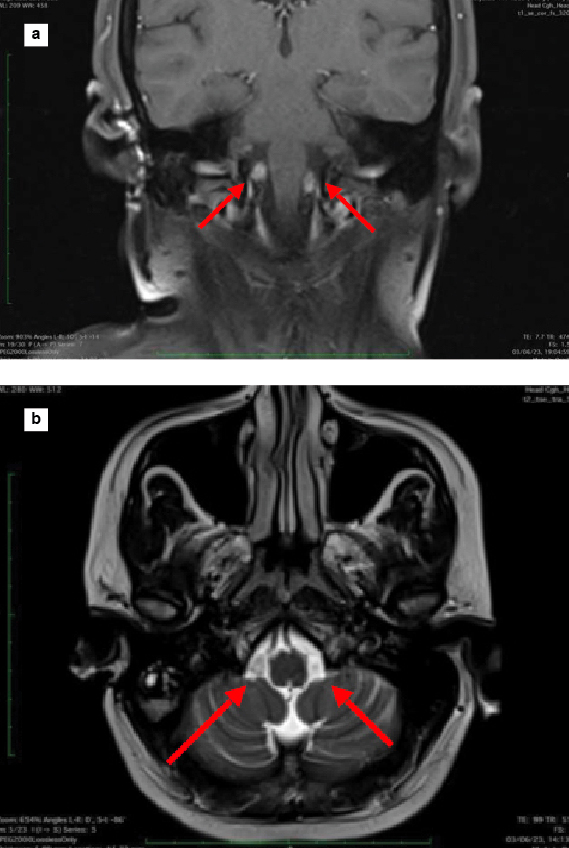

Nerve conduction study revealed bilateral lower limb sensory-motor axonal and bilateral upper limb sensory axonal polyneuropathy2. As a part of routine investigation and to exclude structural pathology, magnetic resonance imaging (MRI) brain with spine contrast was done, which revealed two well-defined T1 hypointense and T2 hyperintense mildly enhancing lesions of size 7 × 4 mm on right and 8 × 4 mm in left lateral cerebellomedullary cisterns with no diffusion restriction or mass effect over adjacent structures suggestive of bilateral hypoglossal schwannoma (Fig. 5 a and b)3. Sural nerve biopsy showed severe axonal neuropathy with no granulomas, inflammation, storage material, or amyloidosis (Fig. 6). Fite-Faraco stain for Mycobacterium leprae was negative. CMT diagnosis is a comprehensive approach that involves clinical findings, electrodiagnostic findings and genetic analysis for specific gene mutations.

Figure 5 a and b. MRI T1 coronal contrast (a) and T2 axial (b) showing two well-defined enhancing lesions in lateral cerebellomedullary cisterns suggestive of hypoglossal schwannoma.